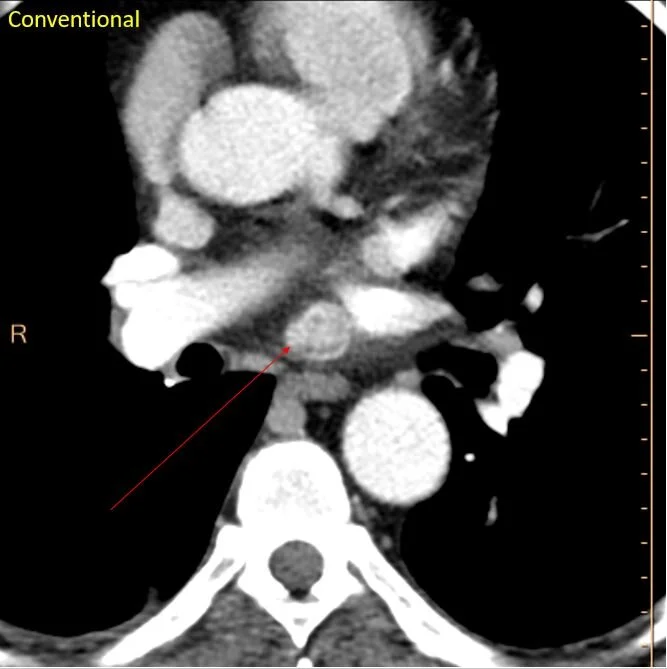

CT a couple of years later. Intensely enhancing subcarinal nodule.

Coronal image shows the nodule is in the roof of the left atrium.